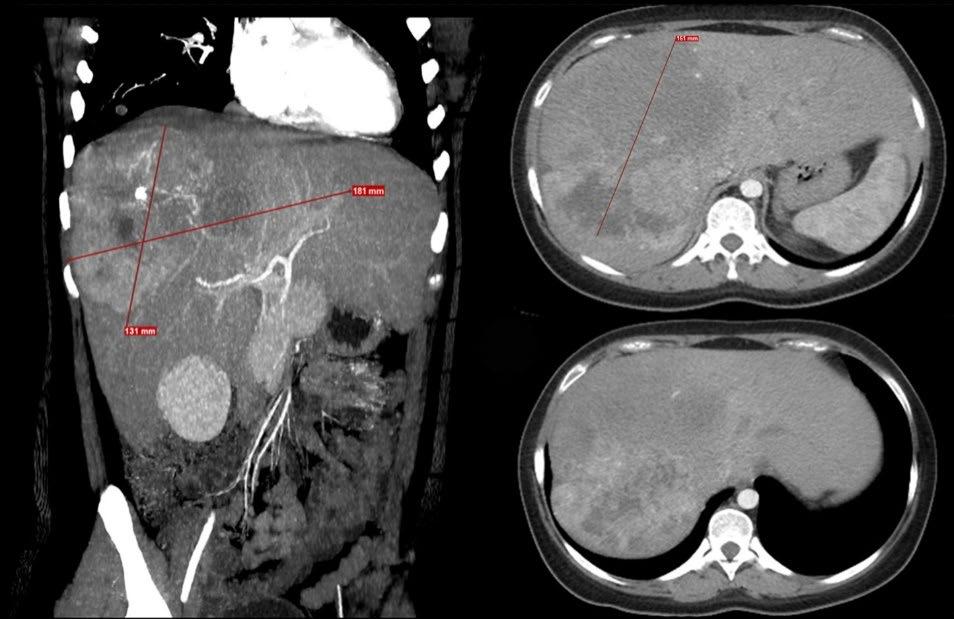

150 Prolonged Survival with Atezolizumab–Bevacizumab and Transarterial Chemoembolization in Unresectable Fibrolamellar Hepatocellular Carcinoma: A Case Report

Espinoza et al.